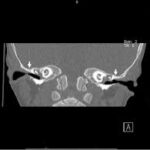

CT Inner Ear Coronal

A CT Inner Ear Coronal scan is an specialized test designed to capture detailed images of the inner ear’s structure. This non-invasive test (does not require surgery or cutting) helps doctors assess a variety of conditions affecting the inner ear, including ear infections, hearing loss, balance disorders, and other ear-related problems. By using coronal CT scan imaging techniques, it allows healthcare professionals to examine the inner ear with great precision, enabling accurate diagnosis and treatment planning.